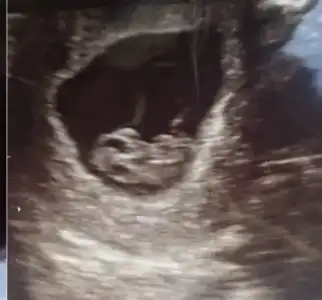

Vajınal kuzum . Ama 10 gun once sağdaydı sımdı solda gezıyor heraldeBu vajinal mı canım vajinal ise kıza benziyor

Soldaki kız canım sagdaki tam emin olmamakla erkek olabilirSeni birde ben darlayabilir miyim ikizlervajinal bakıldı Eki Görüntüle 3252790

10 gün öncesini tekrar at bakim kuzum karından mı oVajınal kuzum . Ama 10 gun once sağdaydı sımdı solda gezıyor heralde![]()

Yok kuzum buda vajına10 gün öncesini tekrar at bakim kuzum karından mı o

Kız senin bebek bildigin yer degiştirmiş yaYok kuzum buda vajına